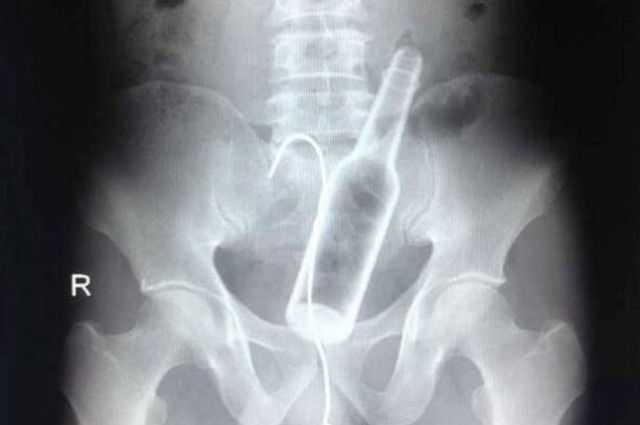

Bottle with a wire inserted to "retrieve" it

Vibrator and tongs

Vibrator in the rectum. The patient attempted self-removal with a pair of salad tongs, which also became lodged.